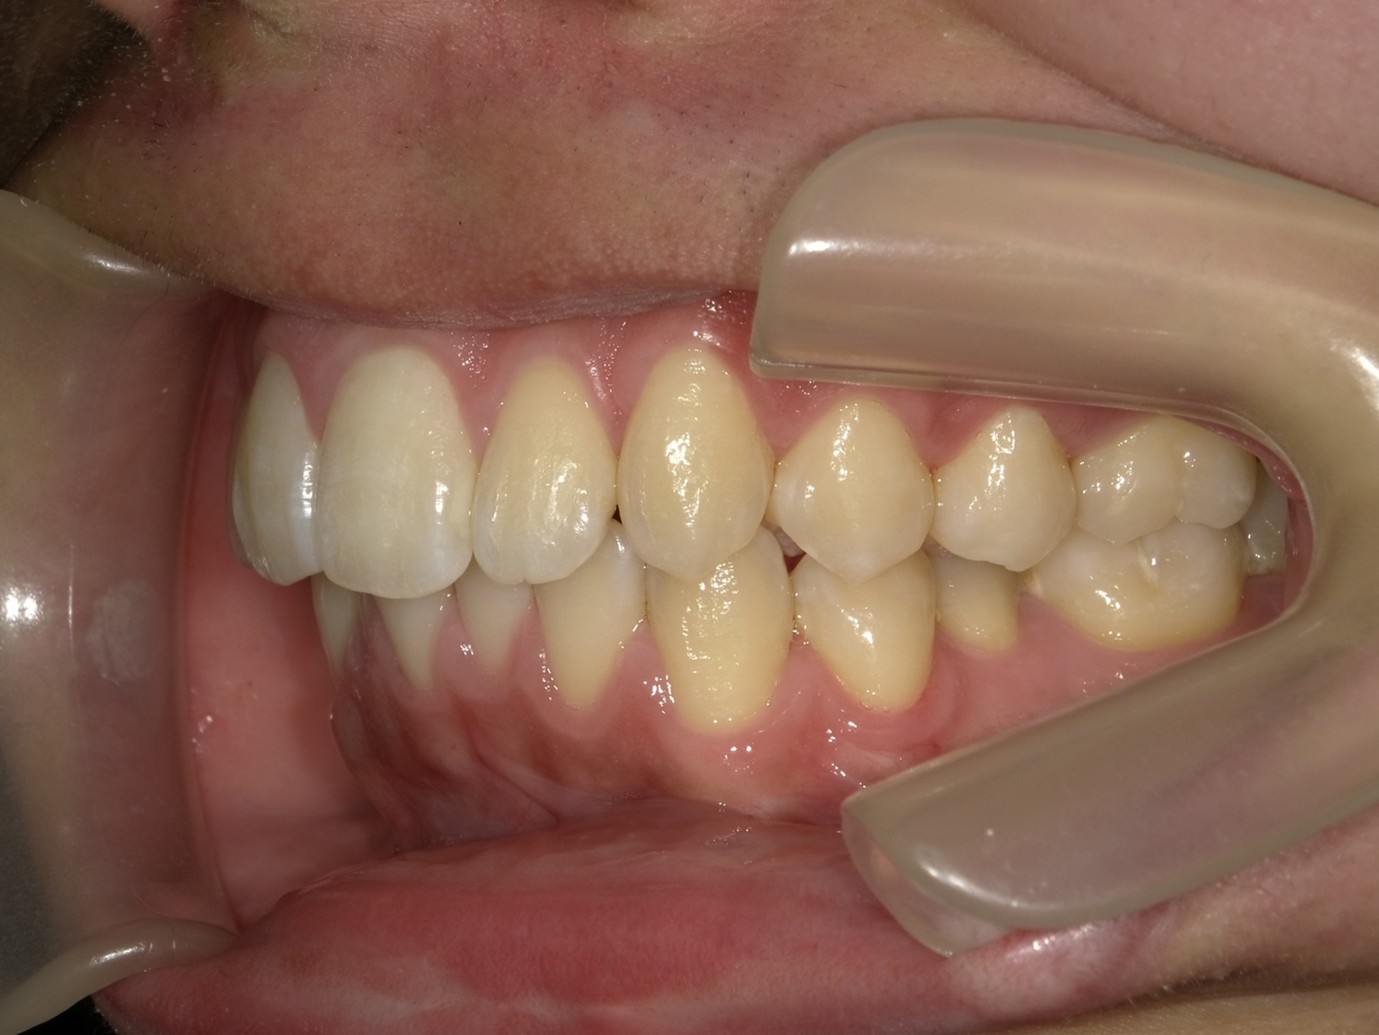

| 症例分類 | 過蓋咬合 |

|---|---|

| 主訴 | 他の歯科医院で咬み合わせを指摘された |

| 年齢 | 10歳10ヶ月 |

| 性別 | 男性 |

| 抜歯部位 | なし |

| 使用装置 | 拡大装置、咬合斜面板(取り外し式の矯正装置) |

| 治療期間 | 3年4ヶ月 |

| 保定装置 | 咬合斜面板 |

| 費用 | 相談料0円、検査料55,000円 動的矯正治療費330,000円 調整料6,600円×30回分 保定装置料0円 |

| リスク・注意点 | 上の顎の大きさに対して下の顎が小さく、過蓋咬合が生じています。これらを改善するために、幅の狭搾している歯列を側方に拡大したのち、下顎の成長を促進しました。

歯の動き方には個人差があり、予想された治療期間が延長する可能性があります。 治療中は矯正歯科装置が歯の表面に付いており、歯が磨きにくくなるため、むし歯や歯周病が生じるリスクが高まります。ハミガキを適切に行ってお口の中を常に清潔に保ち、さらに、かかりつけ歯科医に定期的に受診することが大切です。 矯正歯科装置の使用状況、定期的な通院など、矯正歯科治療には患者さんの協力が必要であり、それらが治療結果や治療期間に影響します。 治療の経過によっては当初予定していた治療計画を変更する可能性があります。保定装置の装着時間が十分確保できない場合、歯並びや、咬み合せの「後戻り」が生じる可能性があります。 上下両側第二大臼歯の萌出を観察する必要があります。(治療後の写真は成人矯正開始直前の資料です。) |